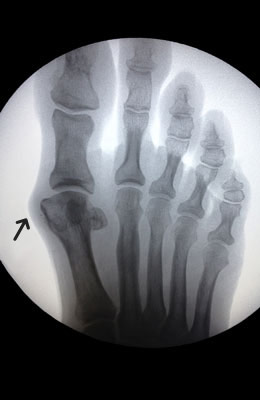

Before

Minimally Invasive Bunion Surgery before

After

Minimally Invasive Bunion Surgery after

Minimally Invasive Bunion Surgery featuring the miniBunon™ System and Tailors Bunionectomy

Melissa is a 32-year-old businesswoman who could not be off her foot post-surgery, yet she had a severely painful bunion. We performed our miniBunon™ System (our trademarked minimally invasive bunion surgery) and had a dramatic correction with no downtime. Melissa continued to work after her bunion surgery and was back in shoes and full activity at 5 weeks. Melissa could not believe the results of her Bunionectomy resulting in no bony bump, no scar and amazing motion. “After” picture taken immediately following surgery. Note the bunion and bunionette (Tailor’s bunion) in the before picture.